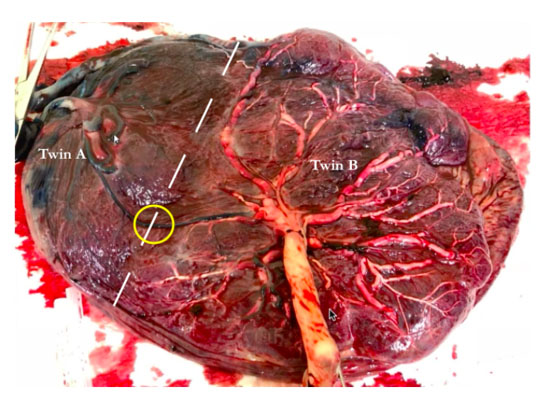

This was the first pregnancy of a 26-year old woman expecting monochorionic twins. She was first seen at 12 weeks and was followed up closely by a fetal medicine specialist with experience in the care of monochorionic twins at least fortnightly. It was obvious that Twin B’s estimated fetal weight was significantly larger than that of Twin A from 15 weeks, and this difference continued to increase as the pregnancy progressed (Figure 1). Discordances were seen in the abdominal circumferences and femur lengths. At 15 weeks gestation, the umbilical artery showed persistently positive end-diastolic flow in Twin A. This suggested that it was type I sIUGR. At 17 weeks, the Doppler studies showed persistently absent end-diastolic flow in the umbilical artery which corresponded to type II sIUGR (Figure 2). This raised concerns regarding the survival of Twin A as there was a 90% chance of deterioration of this fetus. Thus, we considered the following options for the twins: (1) expectant management with close monitoring of their arterial and venous Dopplers, (2) selective laser photocoagulation of the placental vascular, (3) cord occlusion of twin A, and (4) abortion of the whole pregnancy. With type II sIUGR diagnosis, cord occlusion of the umbilical cord of Twin A was considered to eliminate the risk of acute twin-to-twin transfusion from the bigger to the smaller twin if the smaller twin was to die in-utero. Three days later, a repeat scan, however, showed, intermittently absent and reverse end-diastolic flow of the umbilical artery (Figure 3). This changed the diagnosis to type III sIUGR. This case, thus, showed unique Doppler changes from a classification of type I to II to III sIUGR. The intermittent nature of the Doppler studies of the umbilical arteries could explain why it was first thought to be type I, then type II, and finally, type III sIUGR (Figure 4). At 32 weeks, head circumference for both Twins A and B were similar, whereas the abdominal circumferences and femur lengths for Twin A were significantly lower. The timing of the delivery was discussed with the couple and the neonatologist. As the estimated weight discordance was large at about 50% (2 and 1 kg for the Twins B and A, respectively), and the possibility of an unexpected death of the smaller twin with risk of death and morbidity to the other twin was significant, a joint decision was made to deliver the babies at 32 weeks. Corticosteroids were administered and caesarean section was performed. At delivery, the weights of Twins A and B were 1.8 and 1.2 kg, respectively, with birth weight discordance of 30%. The placenta was examined. The veins were injected with white dye and arteries injected with blue dye. Twin B’s bigger umbilical cord was centrally inserted, while that of Twin A was marginally inserted (Figure 5). The vascular equator is along the dotted line, where it shows that about 75% of the placenta belong to Twin B, while the other 25% belong to Twin A. The unequal placental sharing and the presence of an AAA (circled) validated the sIUGR type III diagnosis as these are known characteristics of this diagnosis (Figure 5). Both babies are developing well although there was mild respiratory distress syndrome (RDS) in the first few days that subsequently resolved.

Figure 5: Monochorionic placenta with the vascular equator approximately along the white dotted line. The veins were injected with white dye and arteries injected with blue dye. The arterio-arterial anastomosis typically found in sIUGR type III twins circled in yellow.